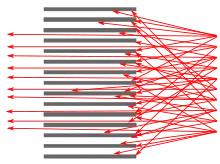

SPECT imaging is performed by using a gamma camera to acquire multiple 2-D images (also called projections), from multiple angles. A computer is then used to apply a tomographic reconstruction algorithm to the multiple projections, yielding a 3-D data set. This data set may then be manipulated to show thin slices along any chosen axis of the body, similar to those obtained from other tomographic techniques, such as magnetic resonance imaging (MRI), X-ray computed tomography (X-ray CT), and positron emission tomography (PET).

To acquire SPECT images, the gamma camera is rotated around the patient. Projections are acquired at defined points during the rotation, typically every 3–6 degrees. In most cases, a full 360-degree rotation is used to obtain an optimal reconstruction. The time taken to obtain each projection is also variable, but 15–20 seconds is typical. This gives a total scan time of 15–20 minutes.

Multi-headed gamma cameras can accelerate acquisition. For example, a dual-headed camera can be used with heads spaced 180 degrees apart, allowing two projections to be acquired simultaneously, with each head requiring 180 degrees of rotation. Triple-head cameras with 120-degree spacing are also used.